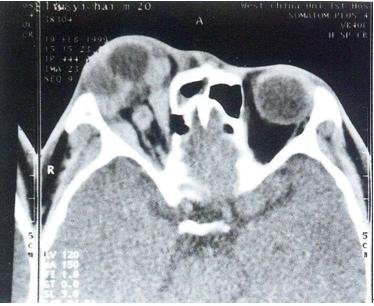

特发性眼眶炎性假瘤CT(弥漫性炎)

特发性眼眶炎性假瘤CT(弥漫性炎):左眼眶内病变弥漫性增生,与周围组织界限不清,眼球受压变形。